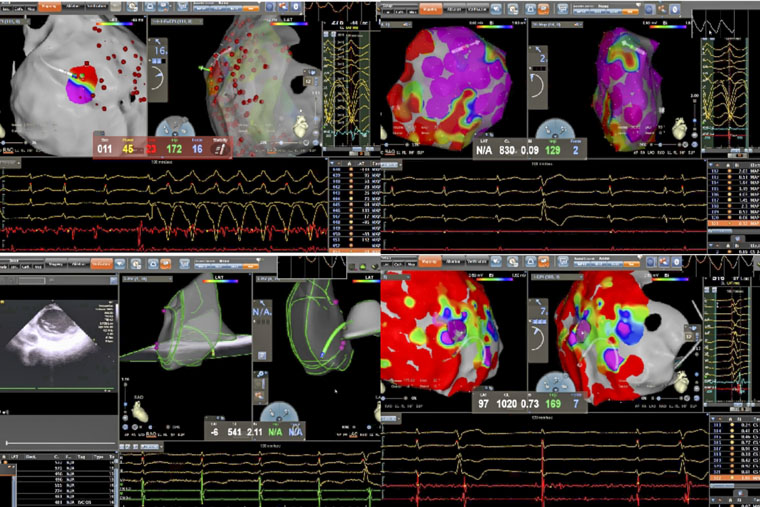

病理性室速通常指由器质性心脏病(如心肌梗死、心肌病等)所导致的室性心动过速。一名患者所患的ARVC,是一种以右心室心肌被纤维脂肪组织替代为特征的遗传性疾病,异常的心肌结构易形成异常电传导通路,从而引发药物难以控制的恶性室速,传统治疗难度大、复发率高。术中,手术团队在X线透视引导下施行心包穿刺,有效规避冠状动脉及心肌损伤风险,为心外膜途径消融建立安全通道。在此基础上,同步进行心内膜及心外膜高密度标测,于右心室多部位识别出低电压区、延迟电位等异常电活动特征,精准判定参与心动过速的关键区域,依托三维电生理标测系统,完成了心内膜与心外膜联合消融。

另一名患者为61岁男性,术前发现频发室性早搏(24小时超过10930次),部分呈三联律及短阵室速,心电图提示起源点为左室乳头肌。频发室早对即将接受大型癌症手术的患者构成多重威胁,如麻醉可能诱发恶性心律失常、室早会影响血流动力学稳定、心脏问题还可能延误肿瘤手术时机。心内科与胃肠外科、麻醉科迅速启动MDT讨论,一致认为必须在肿瘤手术前根除室早这一“定时炸弹”。团队即刻启用“电生理第三只眼”——心腔内超声(ICE)引导手术:ICE导管送入心腔,实时显示左室内乳头肌形态、位置及导管贴靠情况;在ICE引导下克服乳头肌移动难题,实现稳定贴靠与精准消融;ICE实时监测心包情况,极大避免并发症的发生。术后患者室早完全消失,心脏风险解除,并于次日顺利接受贲门癌根治术,现已康复出院。